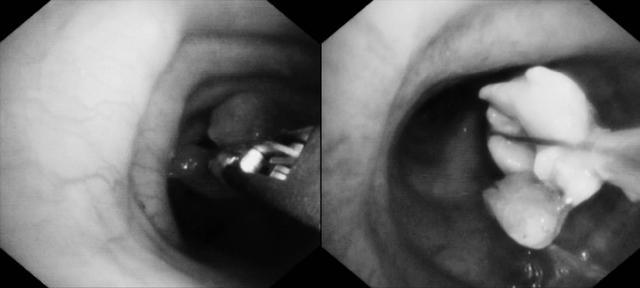

历时整整一小时的持续“毫米级”作业,团队凭借默契的配合与精湛的技术,终于将气道内的堵塞物成功清除。随着气道恢复通畅,患者氧合指标迅速改善,最危急的关卡被成功突破。

(▲清理后隆突镜下画面)

(▲清理后左主镜下画面)

(▲清理后右主镜下画面)